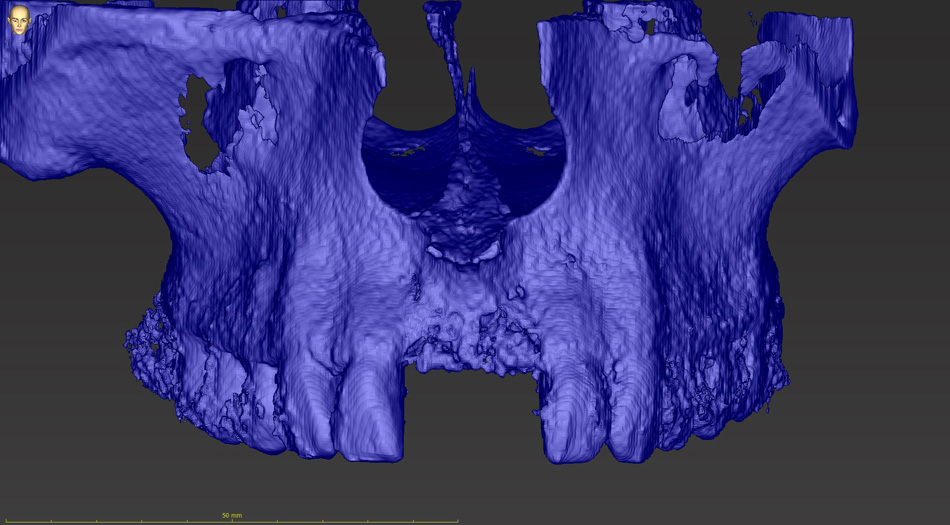

Principem řízené navigace pomocí chirurgických šablon je pasivní vedení zahlubovacích a rozšiřovacích vrtáčků do čelistní kosti na základě předem naplánované přesné pozice, směru, sklonu a hloubce jednoho nebo více implantátů.

Chirurgicko-protetický plán vychází z 3D rentgenu čelisti, otisku zubů a dásně (scanu zubů a dásně) a finálního návrhu protetické náhrady. Na základě těchto dat je v plánovacím softwaru coDiagnostiX vytvořena chirurgická šablona,

Jedná se o externí plánovací program, spojený se zubní laboratoří a frézovacím centrem, který využívá dat získaných z 3D rentgenu čelisti, otisku zubů a dásně (scanu zubů a dásně) a finálního návrhu protetické náhrady.

Tento program umožňuje tříprostorovou počítačovou simulaci při plánování pozic implantátů. Součástí programu je i databáze, ve které mohou být uloženy všechny typy implantátů od všech výrobců, včetně jejich délek, průměrů i tvarů.

Lékař si vytvoří všechny typy zobrazení potřebných pro naplánování – tedy 2D snímky (panoramatický), příčné řezy i 3D model.

Vidí zde i důležité anatomické útvary – čelistní dutinu, průběh nervu atd. Po proměření množství kosti – šířky i výšky vybere z databáze vhodný typ implantátu a umístí ho do požadované lokality. Ihned vidí jeho pozici ve všech 3 rovinách